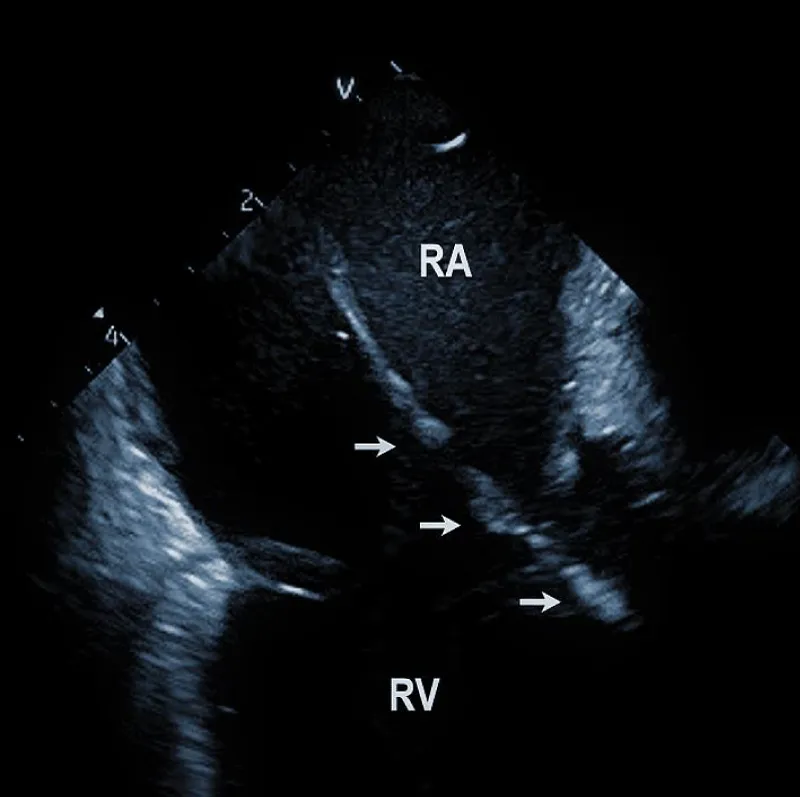

At the beginning of the procedure, ICE is introduced into the right ventricle to check and document possible pericardial effusion and left or right ventricular function. The course of the lead within the right ventricle is visible (Figure 1A). In addition, attachments of the right ventricular leads to cardiac structures could be seen, and the tip of the lead can be localized (Figure 1B).

Figure 1A: The course of two pacemaker leads (arrows) within the right ventricle (RV). The ICE catheter is positioned in the basal RV.

Figure 1B: ICD lead crossing the tricuspid valve between the right atrium (RA) and right ventricle (RV). Arrows mark lead adherent echodensities. The ICE catheter is positioned in the RA.

From the right atrial position, the course of the lead (or leads) could be overlooked. This is the best view to observe the presence of tricuspid regurgitation and the existence and location of lead adherent echo densities (LAE). Positioning the catheter in the superior vena cava or higher enables assessment of the lead attachments or binding sites in this region. Subtotal or total vein occlusion could be detected at the same time.